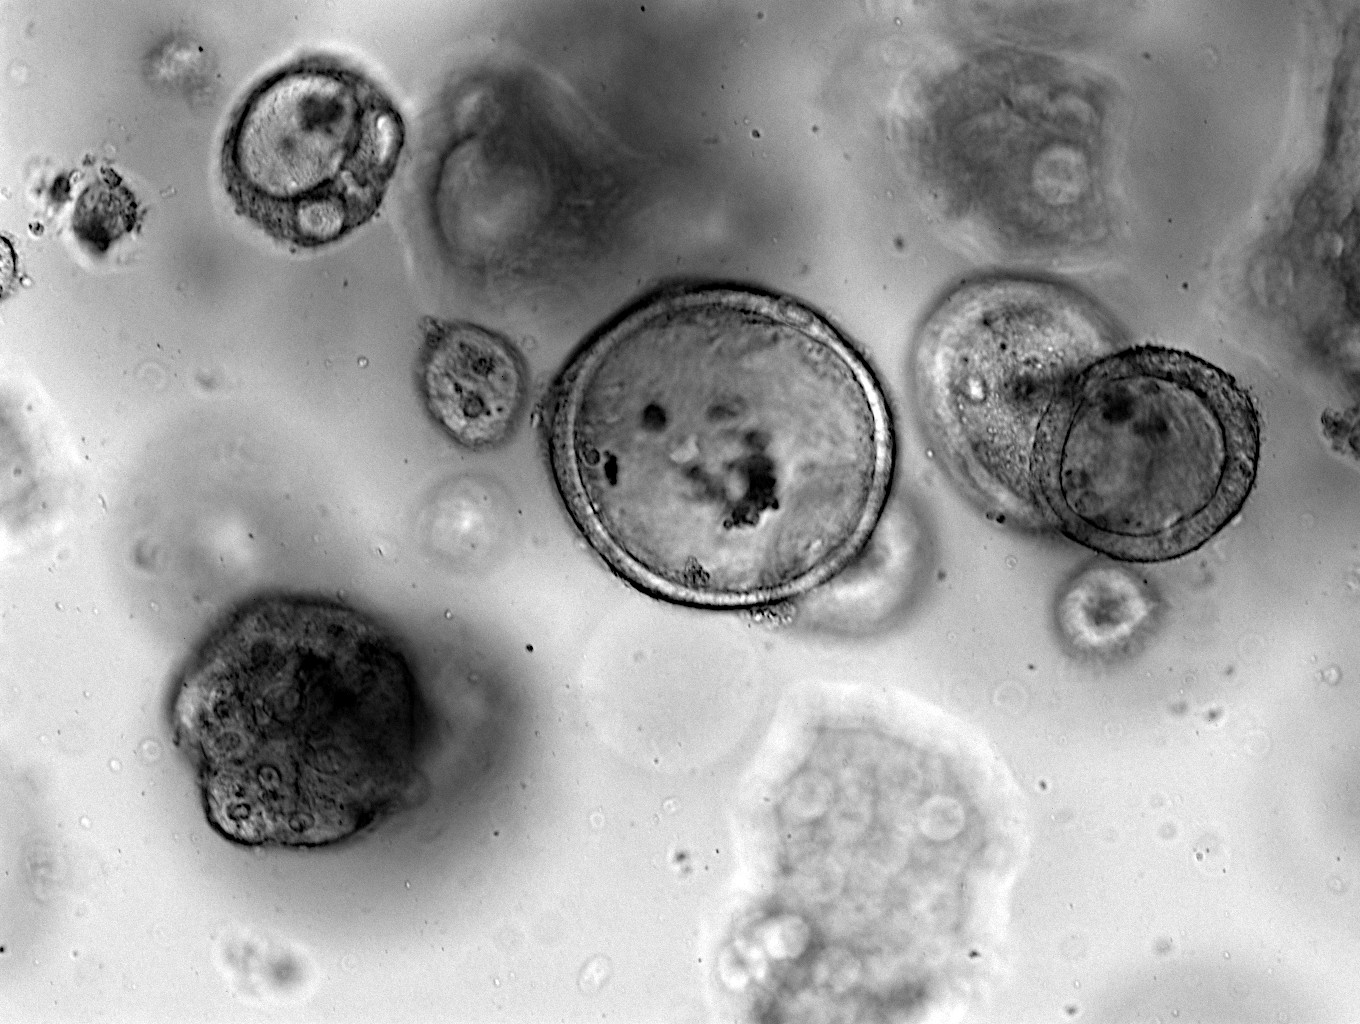

To address this need, the Pancreatic Cancer Team at the Cancer Research Center of Marseille developed RNA-based signatures to predict the efficacy of all drugs used to treat PDAC. They utilized preclinical models such as primary cell cultures (PCC), patient-derived xenografts (PDX), and patient-derived organoids (PDO) to overcome limitations of individual models. The team combined all three models to produce unbiased predictive RNA-based signatures. This signatures were validated in different patient cohorts, showing significant associations with overall, disease-free, and progression-free survival.

- Using a combination of in vitro models (primary cell cultures and patient-derived organoids) and patient-derived xenografts can overcome individual model limitations and produce unbiased RNA-based signatures

- The utilization of methodologies such as PDAC 2D/3D cell models, CRISPR target modulation and real-time proliferation to improve target validation